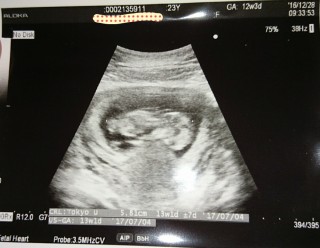

写真:12w3d:ponyoさん

CRL6.4cmに大きくなってました。体全体を跳ね上げるように動いてくれて感動しました!目や鼻もはっきりしてきてますます可愛い(^^)NTの厚みも問題ないみたいで、ひとまずホッとしました。元気にすくすく大きくなってね^_^